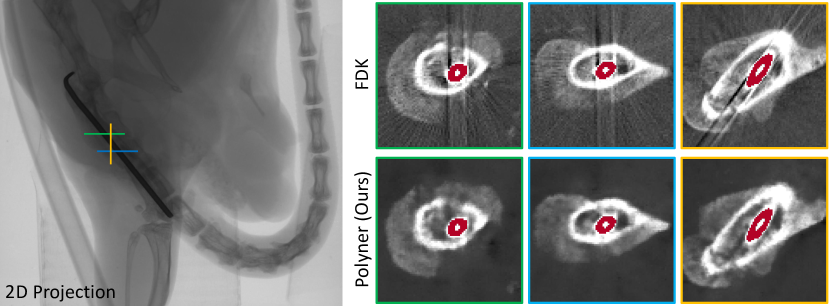

Figure 9: (Left) A sample among 2D projections of a mouse thigh containing a metal intramedullary needle scanned by the micro-CT scanner. (Right) Qualitative results of FDK [49] and our Polyner on the sample. Note that the acquisition geometry is the 3D cone beam. The reconstructed images have a size of 200×\times200×\times150. Our Polyner takes about 32 minutes on a single NVIDIA RTX TITAN GPU. The red regions denote the metal needle tubing. This data collection is approved ethically.